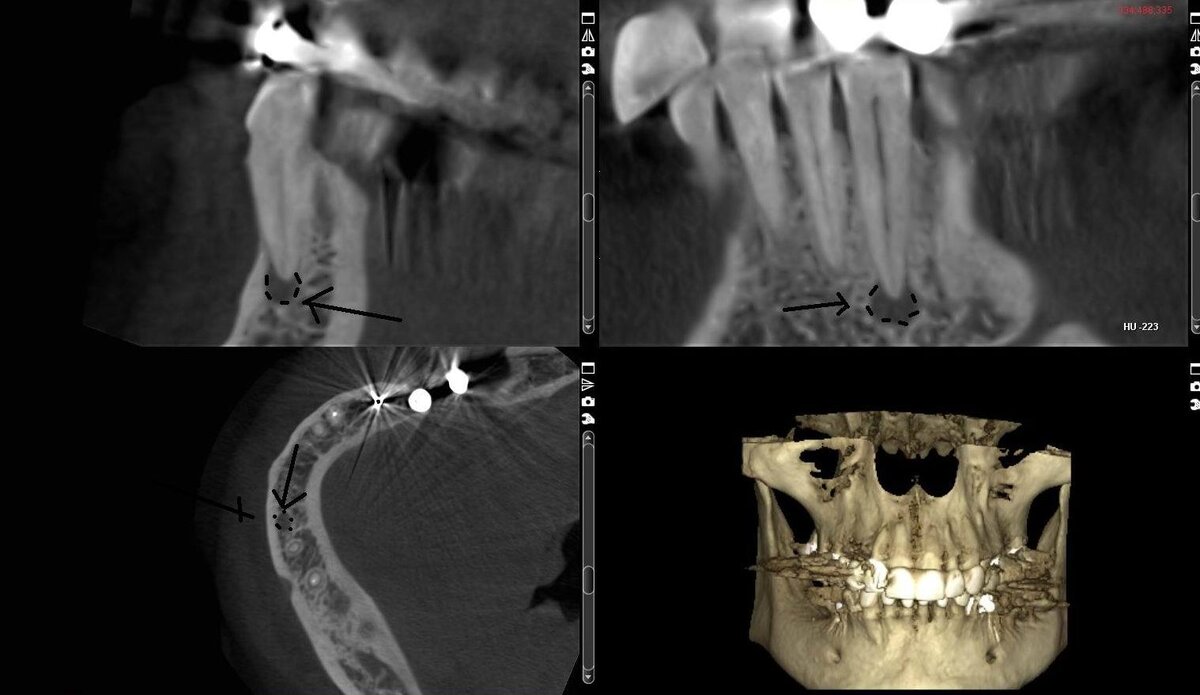

Чаще всего киста зуба обнаруживается совершенно случайно на плановом приеме или перед имплантацией зубов, когда делают компьютерную томографию зубов.

киста у корня зуба с разных ракурсов на КТ зубов

Посмотрите на фрагмент КТ зубов, где киста зуба показана более крупно: